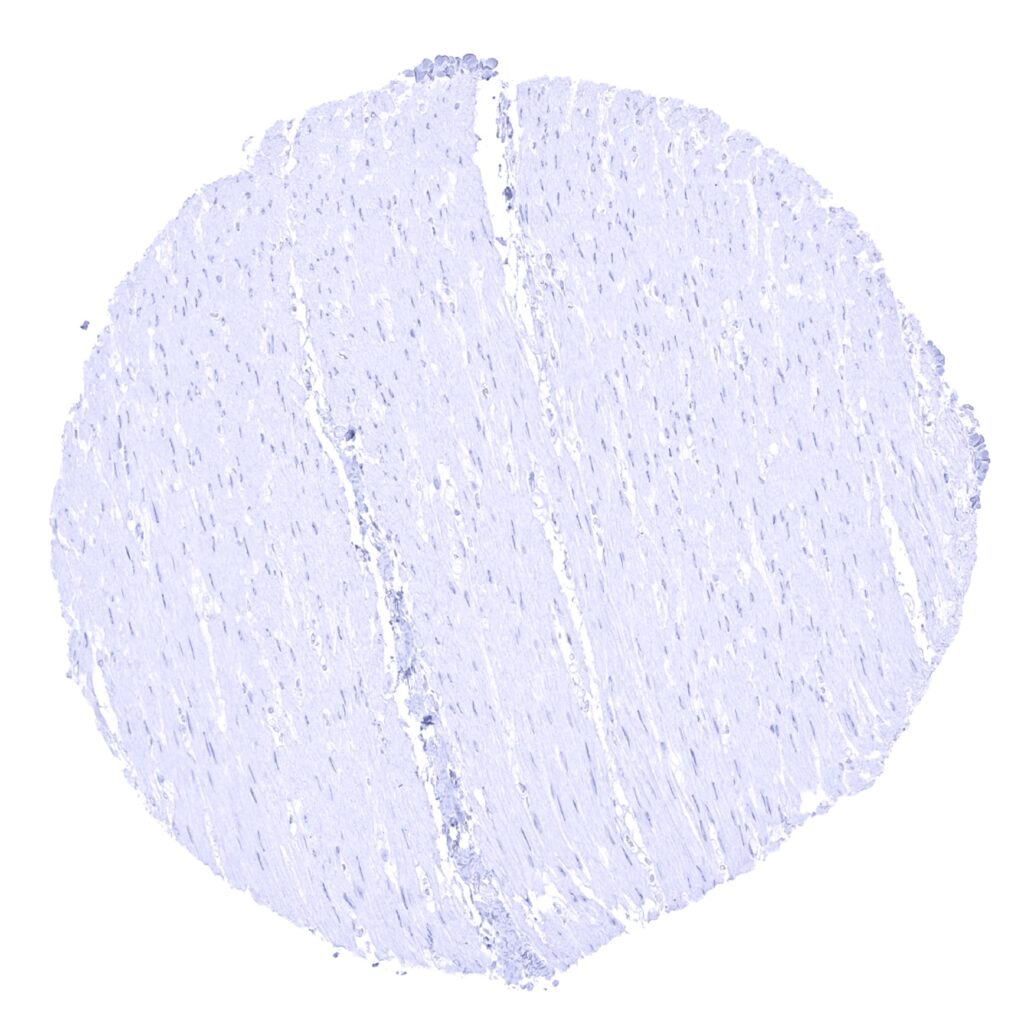

E-Cadherin antibody [MSVA-035R] HistoMAX

Skeletal muscle

Aorta, media